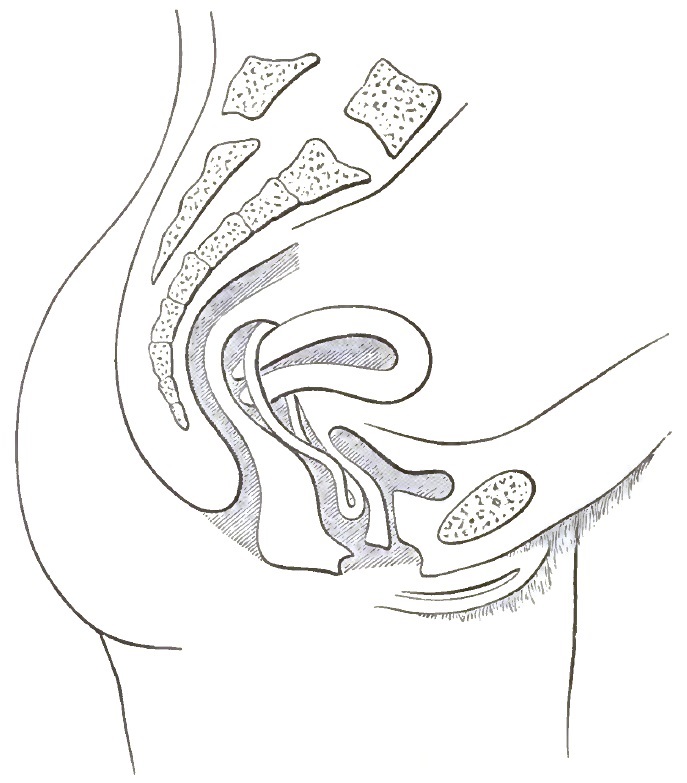

| 2. | THE CORRECT REPRESENTATION OF THE PELVIC ORGANS |

| 15. | EXTREME RETROFLEXION, WITH HYPERTROPHY OF THE CORPUS |